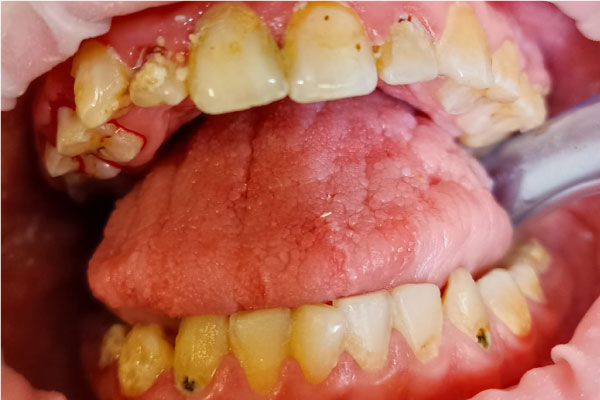

Наши работы

Фото ДО

Фото ПОСЛЕ

Наведите для просмотра

Профессиональная гигиена молочных зубов